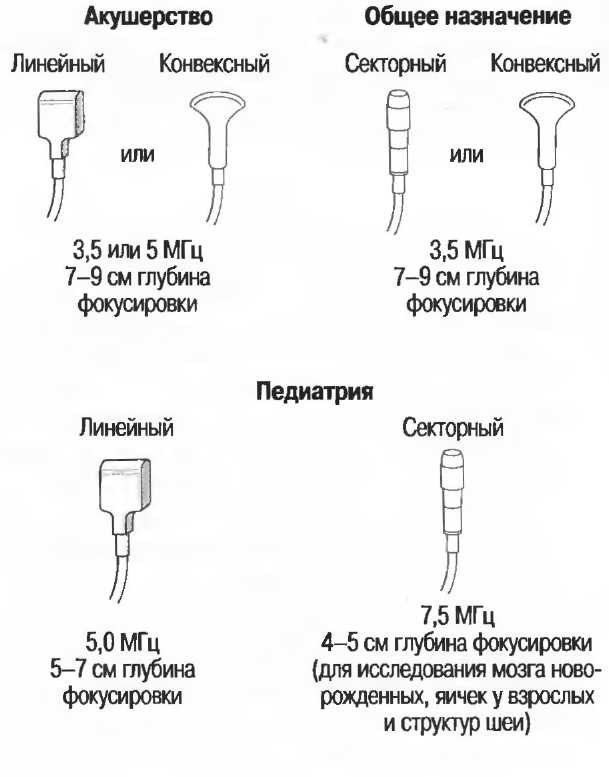

Выбор соответствующего датчика

Наилучшим датчиком для общей практики является конвексный датчик с частотой 3,5 МГц с фокусировкой на расстоянии 7-9 см. Если такого датчика нет, необходимо наличие линейного секторного датчика с частотой 3,5 МГц. При необходимости исследования детей и худых взрослых желательно дополнить набор датчиком с частотой 5 МГц с фокусировкой 5-7 см.

1. Ультразвуковые исследования в акушерстве. Для общих исследований в акушерстве используется линейный или конвексный датчик с частотой 3,5 или 5 МГц с глубиной фокусировки на 7-9 см. Если закупается только один датчик, выбирайте датчик с частотой 3,5 МГц. Датчик с частотой 5 МГц предпочтителен на ранних сроках беременности. В поздние сроки беременности лучше использовать датчик с частотой 3,5 МГц.

2. Ультразвуковые исследования в общей практике. Если проводятся исследования в верхней части живота и таза у взрослых, в том числе и акушерские исследования, предпочтительнее выбор секторного или конвексного датчиков с частотой 3,5 МГц с глубиной фокусировки на 7-9 см.

3. Ультразвуковые исследования в педиатрии. Для детей необходим датчик с частотой 5 МГц с глубиной фокусировки на 5-7 см. При исследовании мозга новорожденного используется секторный датчик с частотой 7,5 МГц с глубиной фокусировки на 4-5 см (этот датчик также используется для исследования яичек и структур шеи у взрослых).